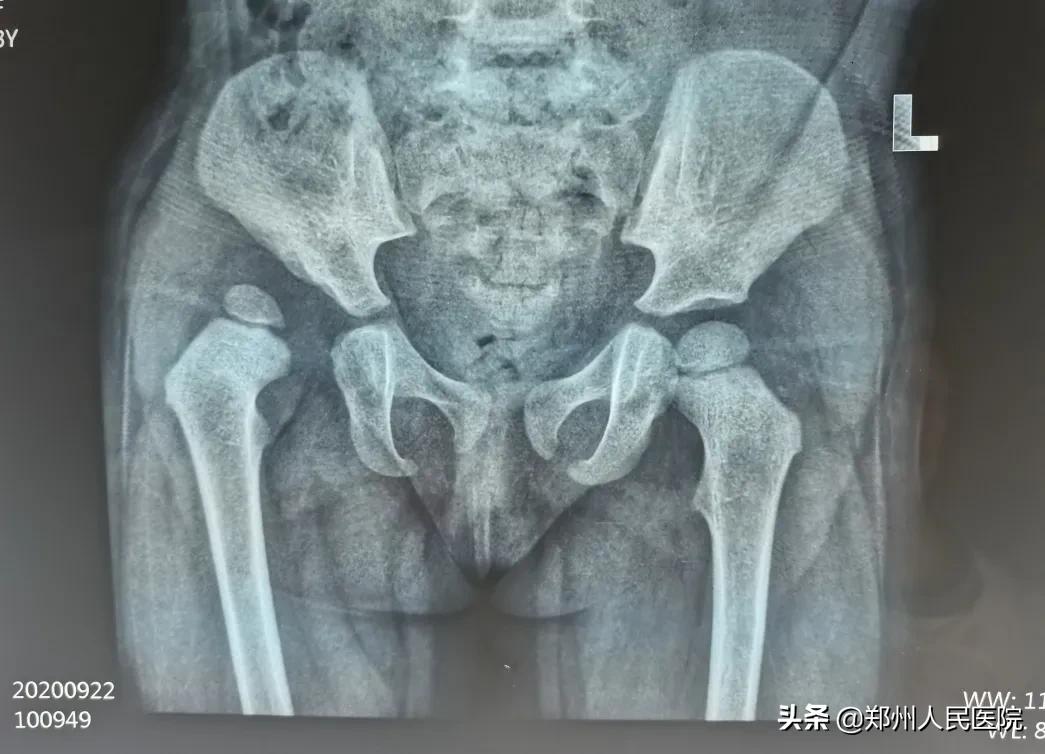

来院后,经过体格检查、走路姿势观察、X光片等,确诊了睿睿也是发育性髋关节发育不良,但是由于错过了最佳治疗时机,孩子只能做截骨手术。

术后

←术后固定

原来通过截骨矫形,把发育不正的髋臼给它矫正到正常位置上来,这样就避免了进一步异常损害。如果任其发展不干预,孩子可能会终生残疾!

“该年龄段的患儿髋关节已开始受力,脱位程度多已加重,骨与软组织的继发改变加剧,保守治疗较难,多采用手术治疗。须通过一系列骨盆和或股骨截骨手术和软组织松解手术,把股骨头安全置入髋臼内,术后联合石膏固定、功能锻炼治疗,能取得比较理想的效果。”骨科三病区副主任医师张保龙说。